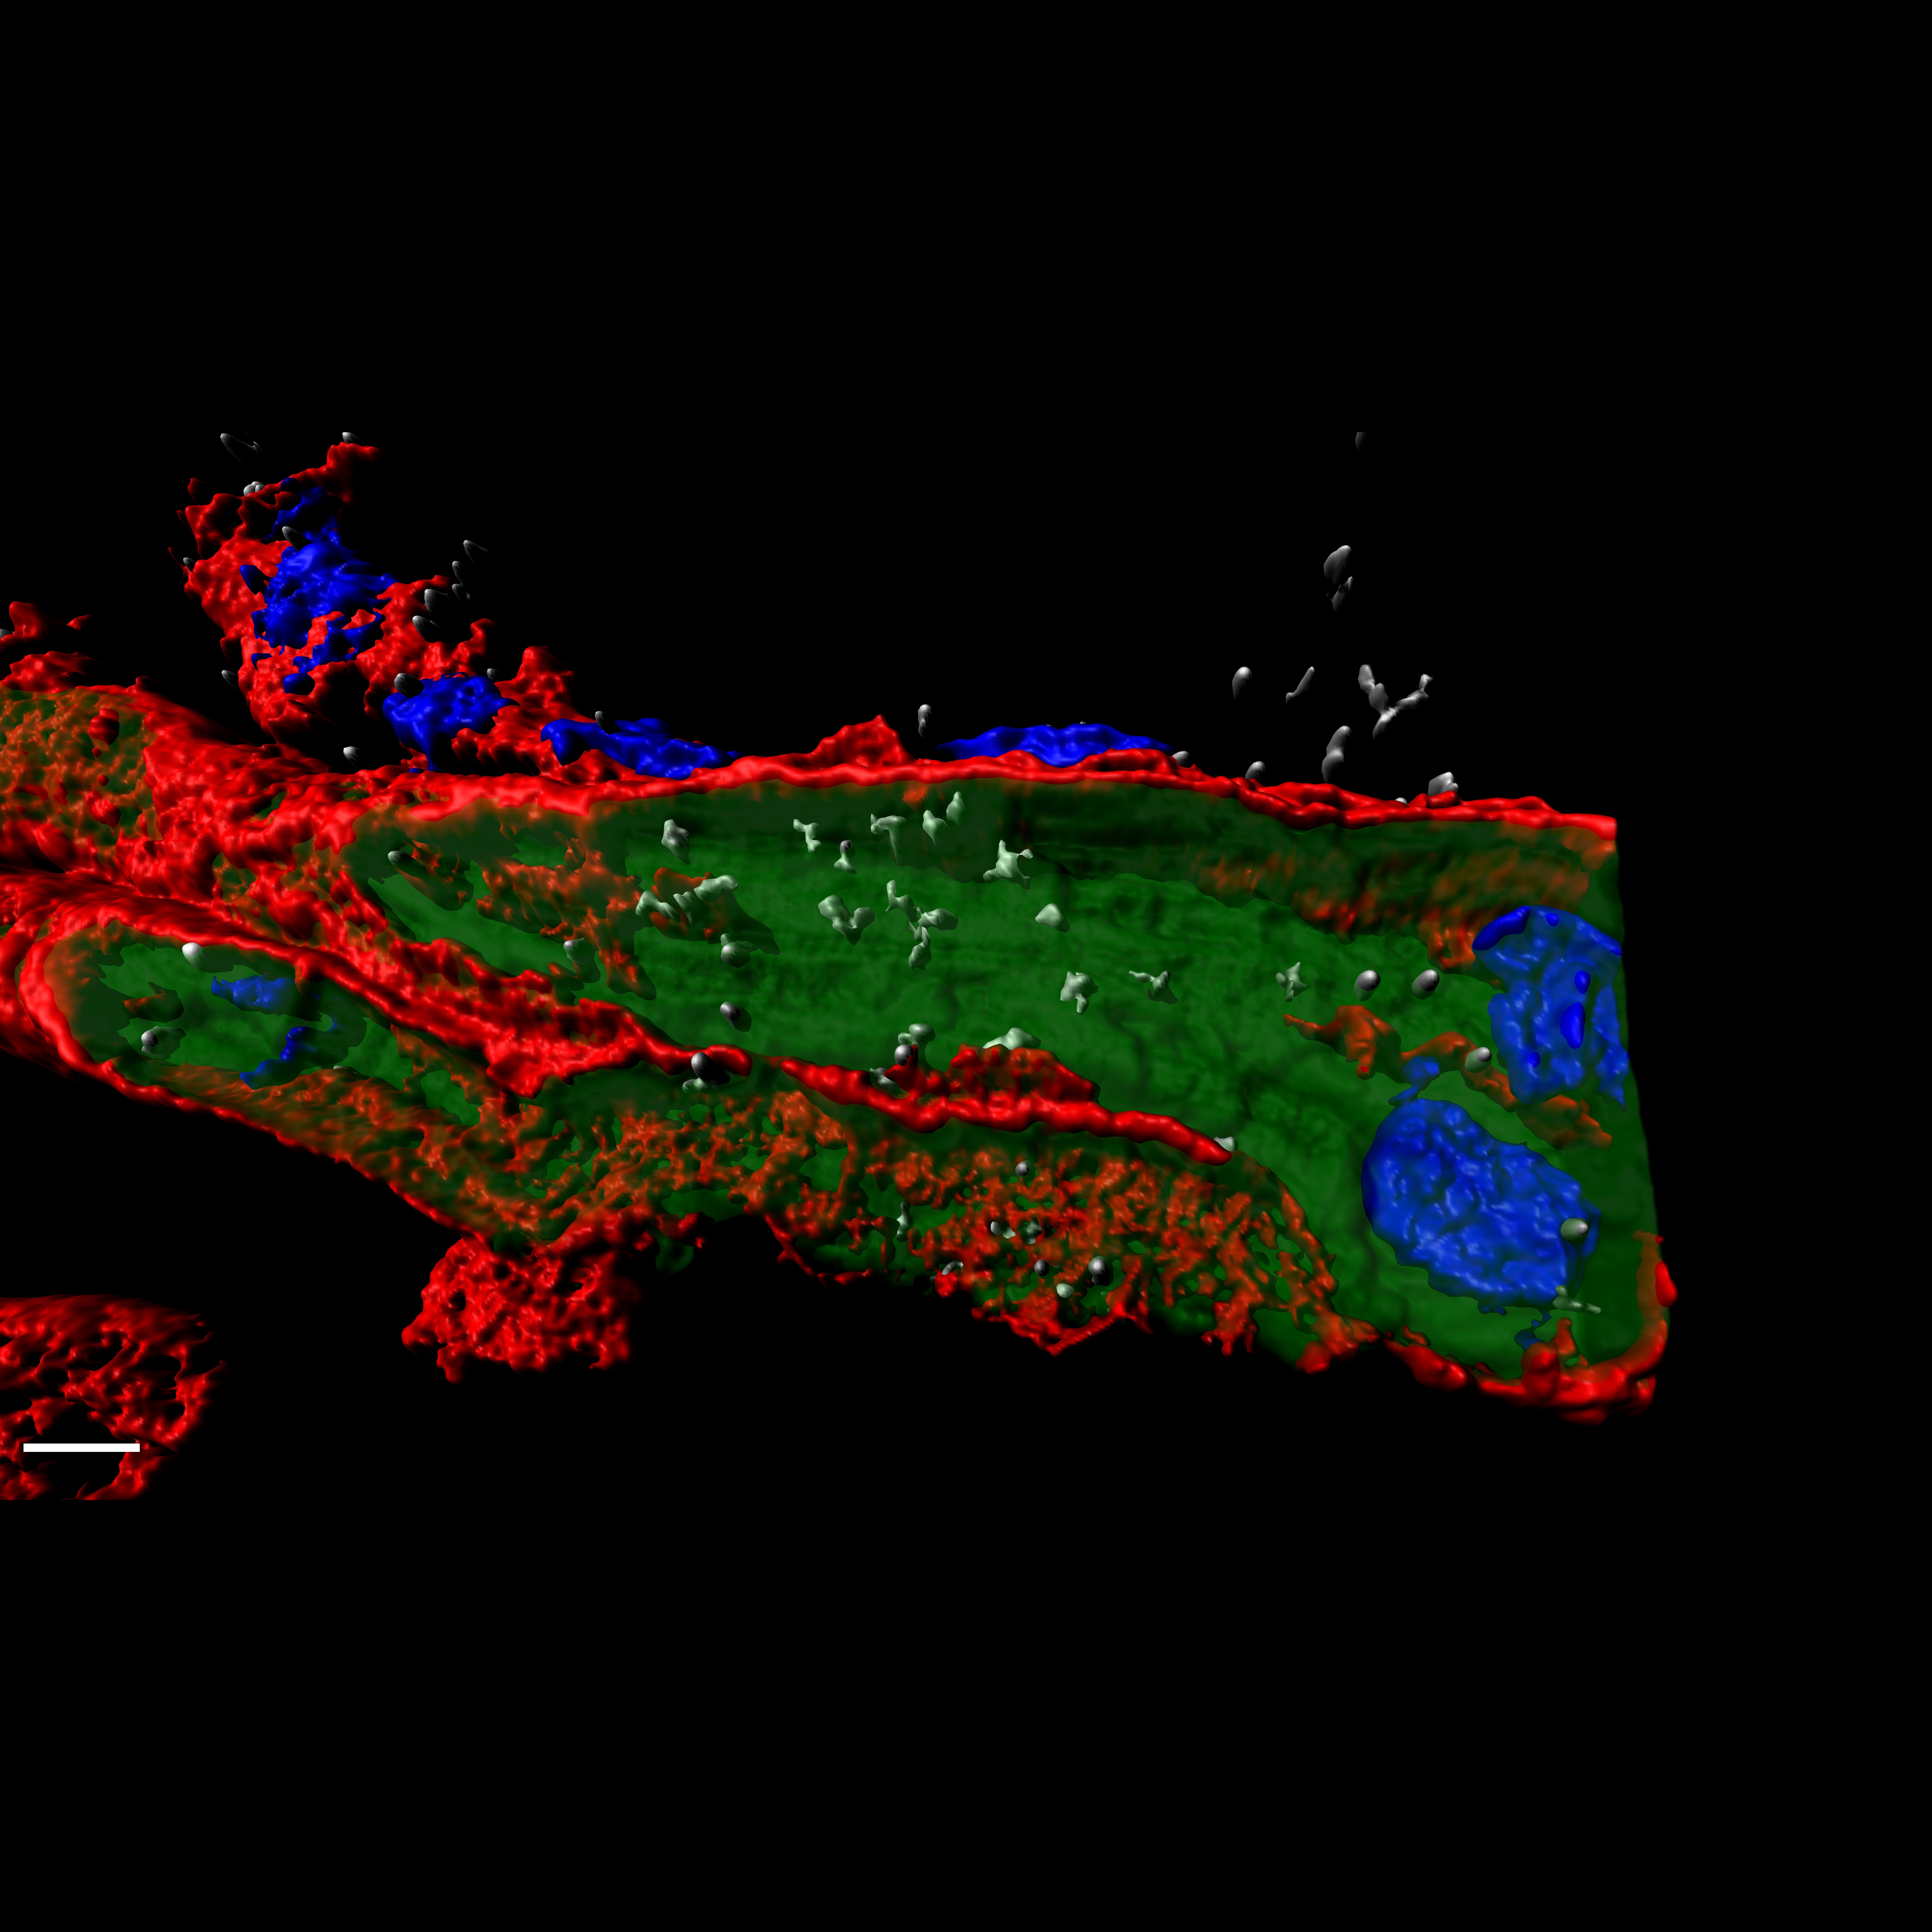

Prueban con éxito una nueva terapia para el cáncer de mama triple negativo en animales preclínicos

22/05/2020